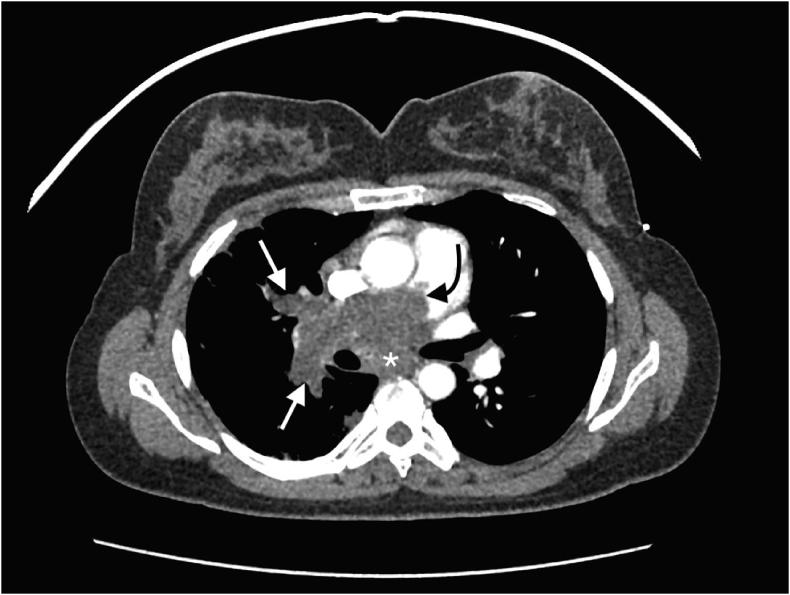

Pulmonary artery sarcoma is a rare malignancy with poor prognosis which can be misdiagnosed as pulmonary thromboembolism. We present a case of a middle age woman who initially diagnosed with presumptive pulmonary embolism that was later found to have pulmonary artery sarcoma. Symptoms, pathology, imaging characteristics and available treatments are discussed.

肺动脉肉瘤是一种预后较差的罕见恶性肿瘤,可被误诊为肺血栓栓塞症。我们报告一例中年女性病例,该患者最初被诊断为疑似肺栓塞,后来被发现患有肺动脉肉瘤。本文讨论了其症状、病理、影像学特征及可用的治疗方法。